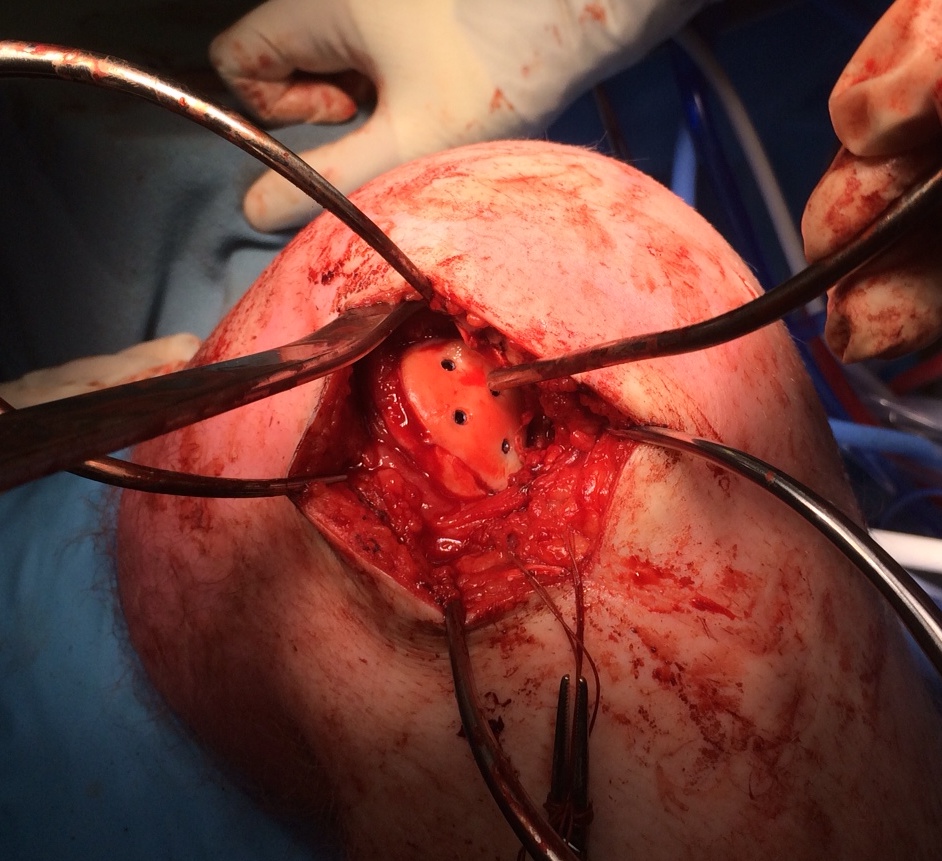

Open bone graft and screw fixation

MFC unstable OCD